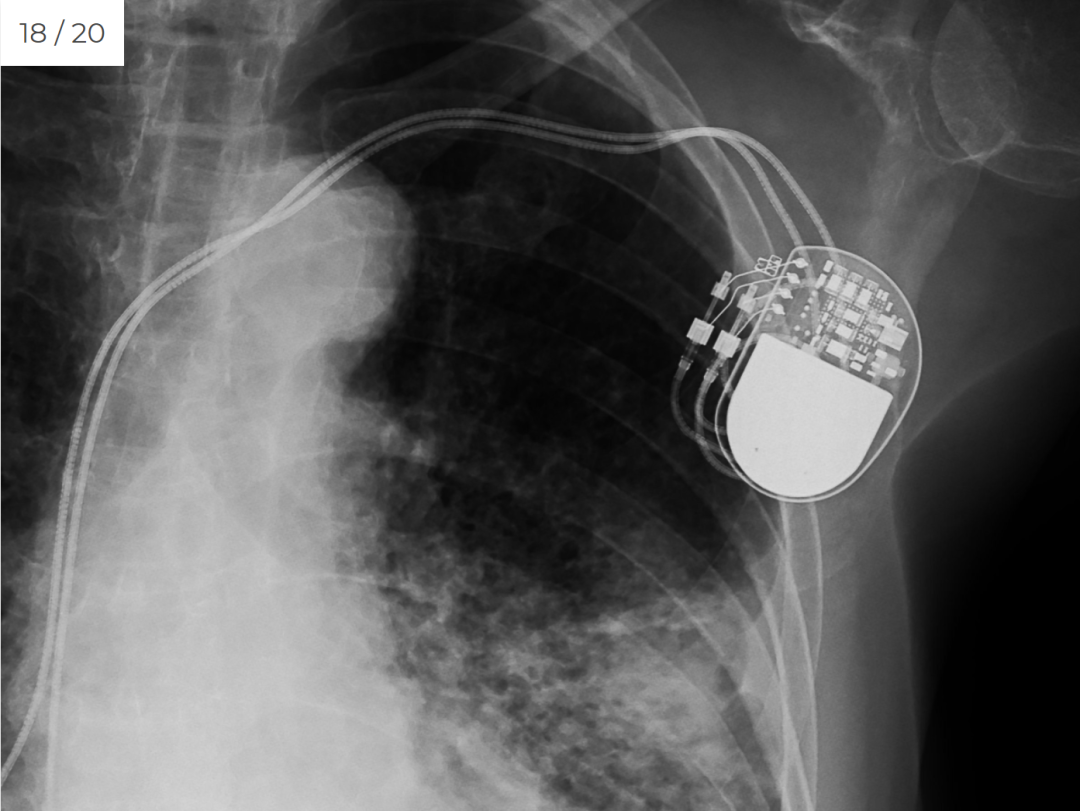

如果没有行李标签,想象一下,无论是乘坐火车、轮船还是飞机旅行,在抵达时存放和定位的行李会是多么混乱。1882 年,新不伦瑞克省的约翰·迈克尔·莱昂斯 (John Michael Lyons) 提出了铁路旅行的“可分离”车票,其中包括乘客信息和目的地。票会被撕成两半,乘客保留一张,另一张留在包里——这是一个跟踪行李的简单系统。这也有助于将丢失的行李与主人重聚。后来,该系统也被用于航空旅行。一位真正的加拿大英雄,新斯科舍省的沃尔特哈里斯卡洛在第一次世界大战期间为皇家飞行队训练时背部受伤,最终四肢瘫痪。尽管有健康问题,他还是创建了多项服务来帮助士兵和退伍军人。二战后,他有了一个新想法:为受伤的退伍军人和其他残疾人制造第一辆轮椅无障碍座椅,可以让他们在社区中保持社交、快乐和活跃。他设计并制造了两辆定制轮椅,后来在汽车制造商的帮助下扩大规模。他的公司 Callow 轮椅在 71 年后刚刚停止运营。加拿大在残疾人出行方面取得了进步。虽然较早的电动轮椅版本可能是在第一次世界大战期间发明的,但现代电动轮椅的功劳归功于加拿大机械工程师 George Klein。1950 年代,克莱因和他在加拿大国家研究委员会的团队设计了一种电动操纵杆操作的轮椅,这是第一个批量生产的电动轮椅,改善了无数退伍军人的生活。该电动轮椅的原始原型,以前在史密森尼博物馆,现在位于加拿大科技博物馆。被加拿大不列颠哥伦比亚医学杂志称为“生物医学工程之父”的约翰霍普斯在研究改善心脏直视手术的方法时提出了心脏起搏器的想法。他意识到电脉冲可以调节心脏的起搏——甚至重新启动它。1950 年代初,在国家研究委员会,他创造了第一个外部起搏器,该起搏器通过插入颈静脉的导管传送电脉冲。这为后来的植入式起搏器铺平道路,霍普斯将从中受益:他在 1984 年植入了一个。如果你曾经想知道为什么美国的钱是绿色的,这就是原因。美国“绿背”的根源可以追溯到加拿大和美国内战。为了避免伪造,银行正在寻找一种不像黑色那样容易复制的墨水——特别是因为造假者经常使用只能拍摄黑白照片的相机来复制纸币。魁北克拉瓦尔大学教授 Thomas Sterry Hunt 于 1857 年提出了绿色,称为“加拿大钞票色调”。美国成为这种色调的粉丝,联盟在其钞票上使用它资助内战。此后,出于传统,美国的钞票上继续使用绿色。胰岛素于 1910 年被发现,但十年后的 1921 年,加拿大医生 Frederick Banting 和他的助手 Charles Best 在多伦多大学 JJR Macleod 的实验室工作,开发出一种方法来分离胰岛素并将该物质注射到动物体内以调节 他们的血糖,这为人类治疗铺平了道路。Banting 和 Macleod 因其创新而获得了 1923 年的诺贝尔生理学或医学奖,这使得糖尿病患者能够更好地控制疾病。